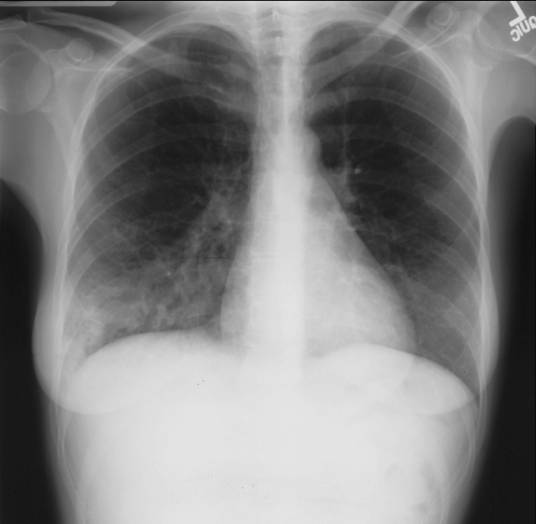

肺部疾病

肺脏本身的疾病或全身性疾病的肺部表现。呼吸系统由呼吸道(鼻、咽、喉、气管和各级支气管)和肺泡组成。肺脏是呼吸系统的主要器官,肺部疾病属于呼吸系统疾病。人体为了完成新陈代谢需要不断从空气中摄取氧气和排出二氧化碳(气体交换),这种气体交换称呼吸。肺与外界环境的气体交换和肺换气──肺泡与血液之间的气体交换称外呼吸(亦叫肺呼吸),气体经过血液运输到达组织后血液与组织细胞或组织液之间的气体交换称内呼吸(亦叫组织呼吸)。故肺脏与心血管系统有着密切的联系。肺脏除了主管呼吸功能外还具备非呼吸性的防御、免疫及内分泌代谢功能。